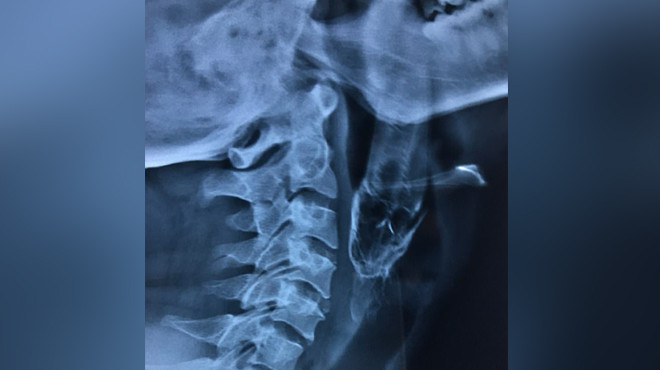

Кеңірдегінде тұрып қалған тірі балық ер адамның тыныс алуына кедергі келтірген. Бұл туралы Қамшы ақпараттық агенттігі life.ru-ға сілтеме жасап хабарлайды. Ауруханаға барған Даш балықты тамағынан алдырта алмаған, оны өзінің үйінен 200 шақырым қашықтықта орналасқан ауруханаға жіберген. Ол ауруханада Дашқа сәтті ота жасалған. Алайда біраз уақыт бойы ол арнайы түтік пайдаланатын болады.